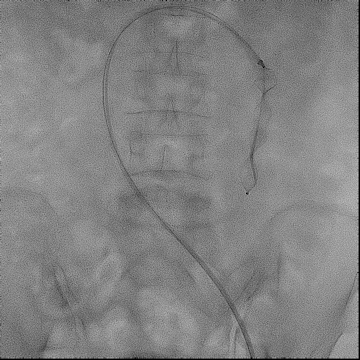

手术过程(二):

使用“Wire In Plug” 技术:在体外释放 20 mm AVP Ⅱ (网盘不解锁),使用穿刺针配合stiff导丝穿过三个网盘,回收至鞘内。